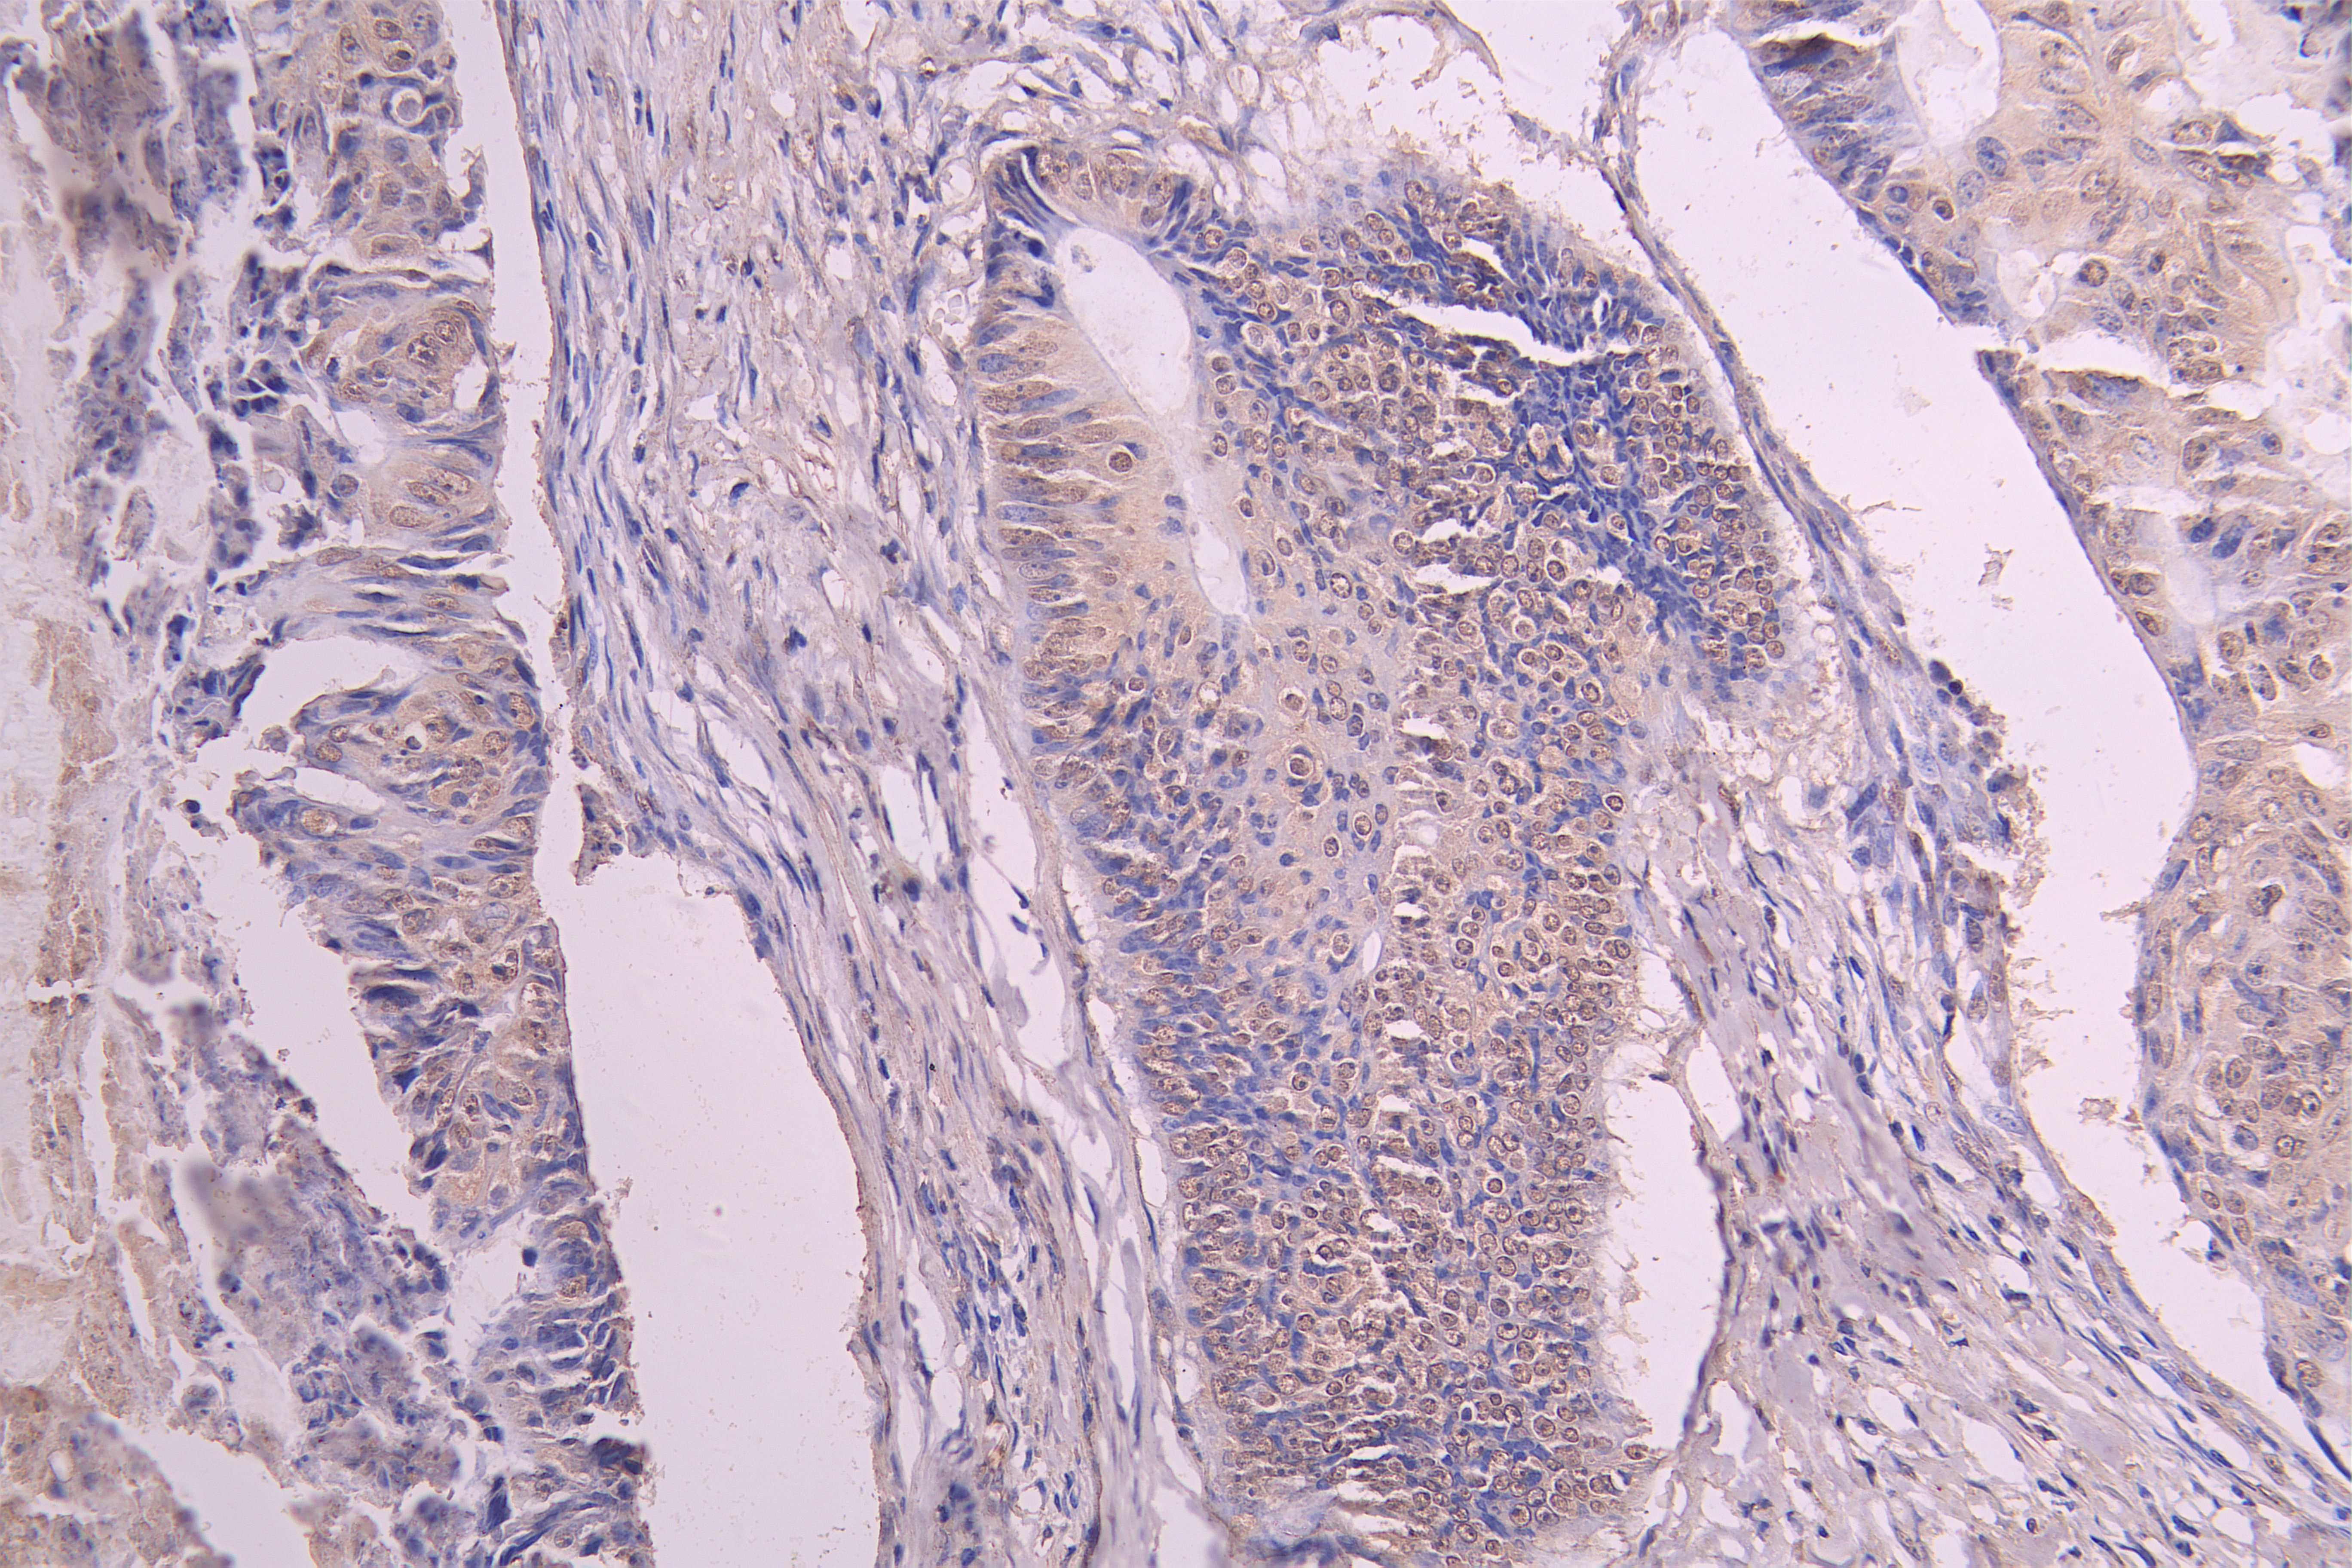

IHC image of CSB-RA009892MA1HU diluted at 1:100 and staining in paraffin-embedded human colon cancer performed on a Leica BondTM system. After dewaxing and hydration, antigen retrieval was mediated by high pressure in a citrate buffer (pH 6.0). Section was blocked with 10% normal goat serum 30min at RT. Then primary antibody (1% BSA) was incubated at 4°C overnight. The primary is detected by a Goat anti-human polymer IgG labeled by HRP and visualized using 0.05% DAB.

IHC image of CSB-RA009892MA1HU diluted at 1:100 and staining in paraffin-embedded human gastric cancer performed on a Leica BondTM system. After dewaxing and hydration, antigen retrieval was mediated by high pressure in a citrate buffer (pH 6.0). Section was blocked with 10% normal goat serum 30min at RT. Then primary antibody (1% BSA) was incubated at 4°C overnight. The primary is detected by a Goat anti-human polymer IgG labeled by HRP and visualized using 0.05% DAB.